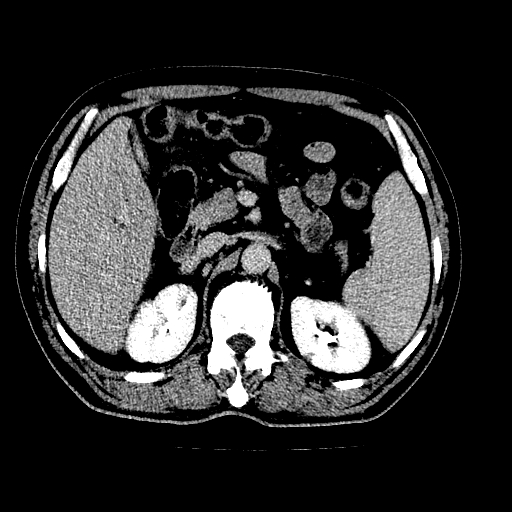

男,66岁,上腹部不适、黄染一周。彩超示:肝左叶占位,肝内胆管扩张,胆总管扩张,胆总管占位?

肝左叶不规则软组织肿块影,边缘不规整邻近肝实质受累分界不清;肝内胆管(左叶)明显扩张成“软藤状”,诊断:肝左叶胆管细胞癌。

肝左叶占位性病变,并胆管扩张,符合胆管细胞癌ct表现,门脉左支受累,左肾囊肿。窗宽太窄了,其他的看不清

左叶胆管细胞癌累及胆总管,门脉左支受侵,慢性胆囊炎胆结石,左肾小囊肿

肝左叶不规则软组织肿块影,边缘不规整邻近肝实质受累分界不清;肝内胆管(左叶)明显扩张成“软藤状”,诊断:肝左叶胆管细胞癌。胆囊钙乳症。